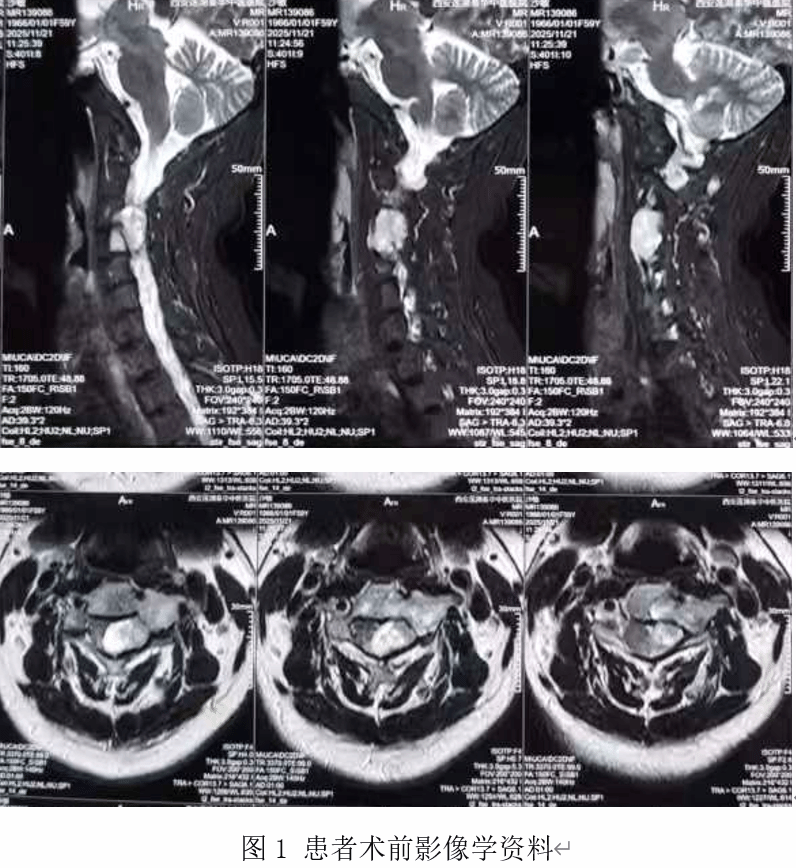

患者近期长时间乘坐飞机后致上述症状再次加重。颈椎磁共振检查显示:颈椎第3-4节段椎管内外存在巨大占位性病变,肿瘤紧邻脊髓、神经根及椎动脉,手术风险极高。面对这一“手术禁区”,李女士多方打听后得知,我院骨科中心主任李浩鹏教授团队在脊柱肿瘤治疗领域享有国际声誉,曾成功完成多例高难度椎管内肿瘤切除术。2025年11月,她毅然跨越太平洋,慕名来院求诊。

入院后,脊柱与骨肿瘤病区主任王栋教授立即组织多学科会诊(MDT),制定手术方案。神经外科、麻醉科、影像科专家联合评估认为:肿瘤体积达28mm×24mm×18mm,且严重压迫颈髓,导致患者左上肢肌力下降至4级(正常为5级),必须尽快手术解除压迫,否则将造成神经功能不可逆受损。但挑战随之而来: